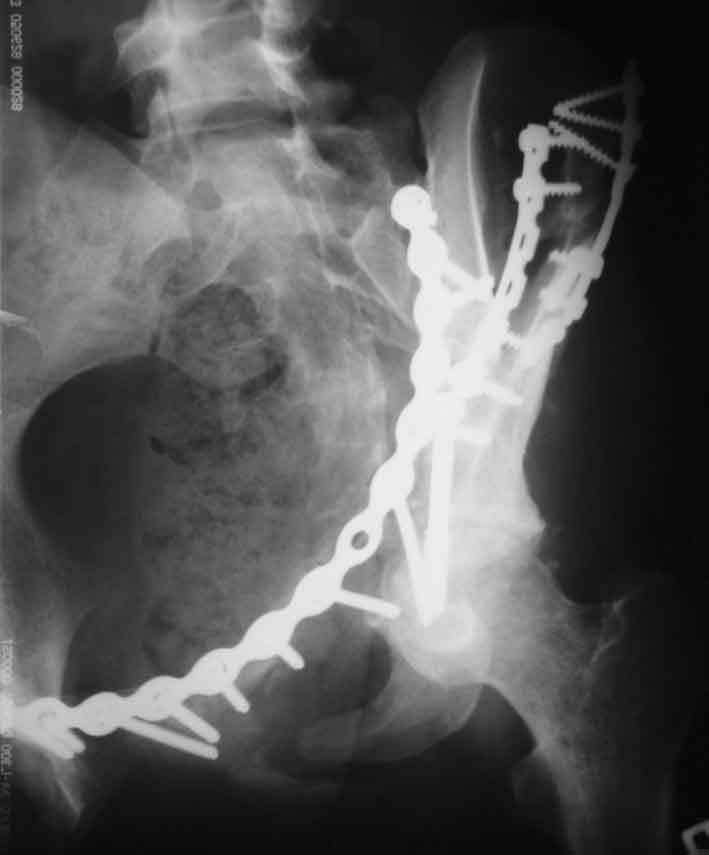

Прямая проекция

inlet

подвздошная

запирательная

По всей видимости, вы имеете в виду канюлированный винт, который проецируется на вертлужной впадине. Та вот, он проведен не через лонную, а седалищную кость. Вертлужная впадина абсолютно интактна. Это хорошо видно на проекции inlet.